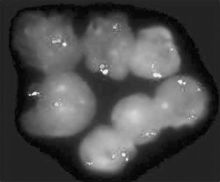

慢性白血病(4)細胞遺傳學:約半數的慢性淋巴細胞白血病出現染色體異常,最常見的數目異常為增加

一個12號染色體(+12),其次可見超數的3號,16號,或18號染色體。常見的結構異常為12和11號染色體長臂相互易位,6號染色體短臂或長臂的缺失,11號染色體長臂的缺失,14號染色體長臂的增加等染色體的改變。有報導,具有“+12”的慢性淋巴細胞白血病患者,從診斷到出現有治療指征的臨床症狀的時期明顯短於無“+12”的對照組,故認為“+12”似乎和短促的病程及不良的預後有關。